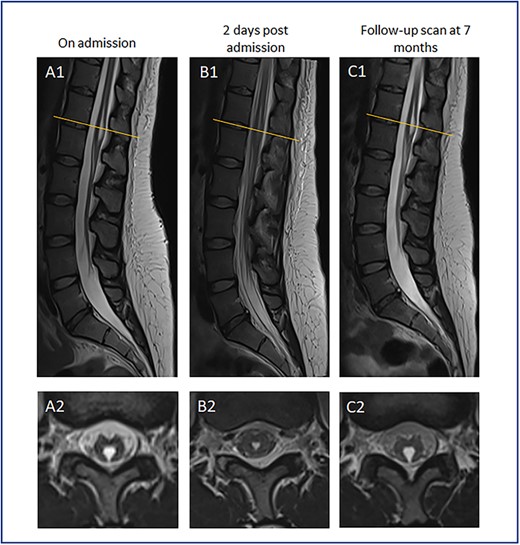

Neurological consultation was sought, and lumbar puncture was performed which revealed a normal cerebrospinal fluid (CSF) profile. On Day 4 of admission she was re-reviewed by the neurologists where she was found to have no movement in her lower limbs (0/5 power). Her lower limb reflexes were present bilaterally with downgoing plantar responses. A whole spine MRI was performed which revealed a TV cyst (Fig. 1). On Day 6, she reported complete resolution of her symptoms with a normal neurological examination. A repeat whole spine MRI was performed which showed spontaneous resolution of the cyst in keeping with cyst rupture. The MRI was deemed normal with no evidence of intracranial pathology as reported by the neuroradiologist.

MR spinal imaging during admission and at follow-up. T2 weighted MR sagittal (A1-C1) and axial (A2-C2) images at T12/L1 level (orange line). A—Admission MRI, B—MRI 2 days post admission, C—7 month follow-up scan. A1 + 2 at initial presentation with expanded TV cyst compressing conus causing acute neurological deficit. B1 + 2 showing conus appearances post TV cyst rupture corresponding with resolution of neurological symptoms. C1 + 2 images at 7 month follow-up in keeping with cyst recollection with no corresponding neurological deficit.

We can only hypothesize rather than prove that the cyst was the cause of this patient’s neurological deficit. The transient neurological signs correlate with the transient results on imaging, whereby the cyst ruptured and later re-expanded again, as discussed below. Neurologist advice was sought, and no other abnormalities in the neuro-axis were found. Hoover’s sign was also negative.

She underwent a short period of inpatient physiotherapy and was discharged home. The patient did not attend further outpatient follow-up. Seven months later she attended her local emergency department with symptoms of bilateral non-dermatomal leg paraesthesia. Lumbo-sacral MRI demonstrated modest enlargement of the TV cyst in keeping with recollection. In the absence of a progressive motor or localizing neurological deficit, surgery was not felt to be indicated and she remains under outpatient surveillance.